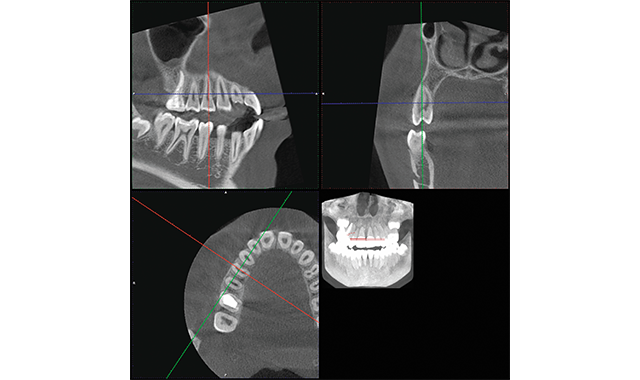

How to use a 3D digital workflow for ortho treatment

3D digital treatment planning and diagnostic case workup can lead to improved patient care.

by Dr. Jay B. Burton

Featured product: Planmeca PlanScan® and Planmeca Emerald™ from Planmeca

The World of 3D Processes in orthodontics has arrived, and the digital workflow necessary to manipulate and work with the information is being developed. Cone beam computed tomography serves as the framework for diagnostics and treatment planning purposes upon which the intraoral, along with potentially a 3D facial analysis, can be added to improve diagnostic capabilities.